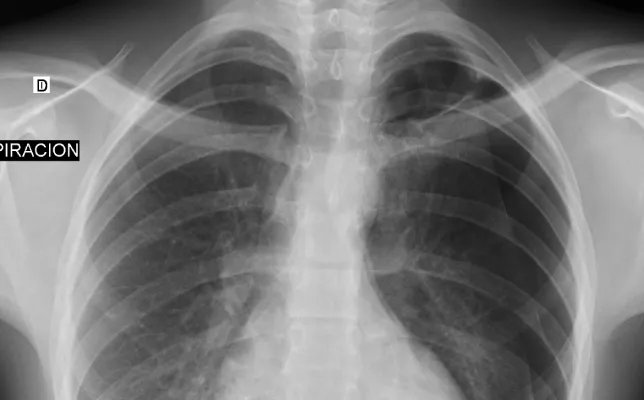

Los casos clínicos presentados corresponden a ejemplos seleccionados de la práctica radiológica, con fines educativos y de actualización profesional. Cada caso incluye hallazgos relevantes, diagnóstico diferencial y comentarios orientados al razonamiento radiológico. Todo el material ha sido anonimizado y se publica respetando los criterios de confidencialidad y privacidad del paciente.